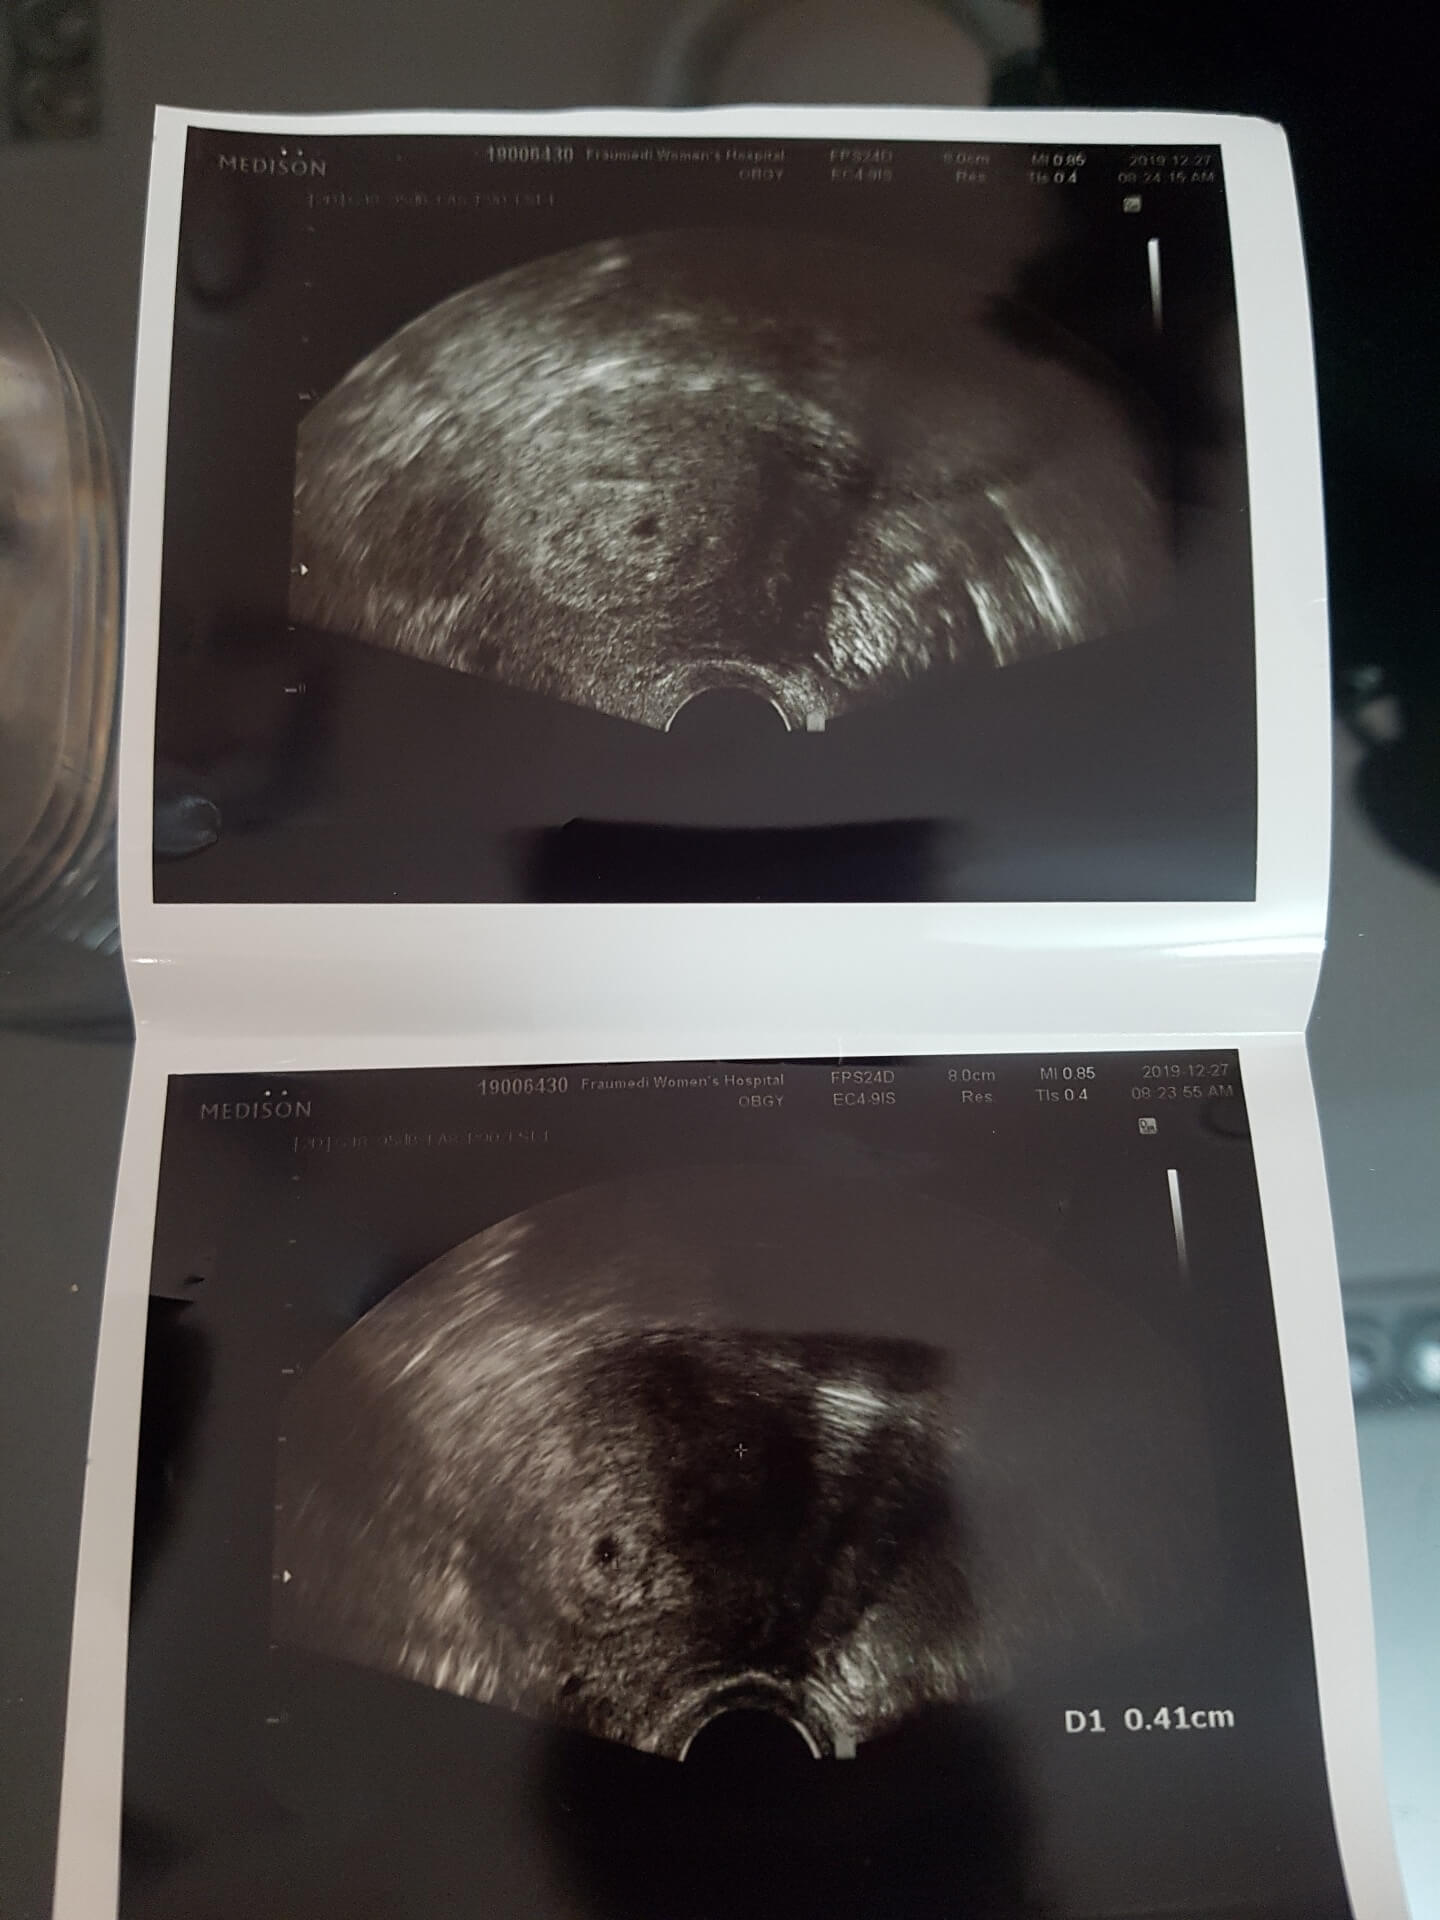

저는 첫째 임신의 경우 결혼하고 바로 아기가 생기고 아기가 생긴 후에도 일을 하고 있었음에도 아기가 건강하게 잘 자라고 입덧하나 없이 출산까지 비교적 수월하게 임신을 유지했던 터라 둘째도 쉽게 찾아올 것이라고 생각했었습니다. 그렇지만 그 생각은 저의 오산이었죠. 둘째를 계획하고 착상까지 이루어졌지만 아기집을 발견하고 다음 주에 검진을 갔을 때 아기 심장이 뛰지 않았죠. 8주까지는 기다려보자는 마음으로 매일 하루가 백 년 같은 마음으로 하루하루를 보냈지만 8주가 지난 후에도 아기의 심장은 뛰지 않았습니다. 계류유산이었습니다.

계류유산이란 아기집은 있지만 아기가 보이지 않거나 20주 이전에 아기가 사망한 후 자궁에 잔류하는 것을 말합니다. 계류유산은 아기의 염색체이상이나 기형 또는 모체의 당뇨 등의 질병 등이 그 원인이 되고 자연유산의 대부분은 계류유산 단계를 거친다고 합니다. 계류유산이라고 확진을 받고 진료실을 나와 보이는 임신부들이 얼마나 부러워 보이던지..